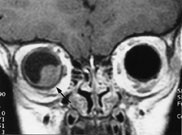

I de tilfeller der ultralydundersøkelse ikke med full sikkerhet kan differensiere mellom primær retinal affeksjon (som Coats sykdom, primær persisterende hyperplastisk corpus vitreum, massiv retinal gliose eller premature endringer assosiert med subretinal væske eller blødning) og sekundære retinale forandringer med mulig underliggende vev, anbefales MR (fig 1). Solide svulster som er større enn 2 mm i tykkelse (retinoblastom, leiomyom, koroidalt melanom og retinalt kapillært hemangiom) er høysignalgivende på T1 og har lavt signal på T2-vekting (fig 2). Ved å vurdere T1-serien kan man skille mellom en enkel effusjon og en mer alvorlig sykdom (4).

En vanlig effusjon er hypo-/isointens, dog kan effusjoner gi litt høyere signal på T1-vekting grunnet høyt proteininnhold. Blødning gir høyt signal. Solid tumor har vanligvis lavere signal på T2-bilder enn væske.